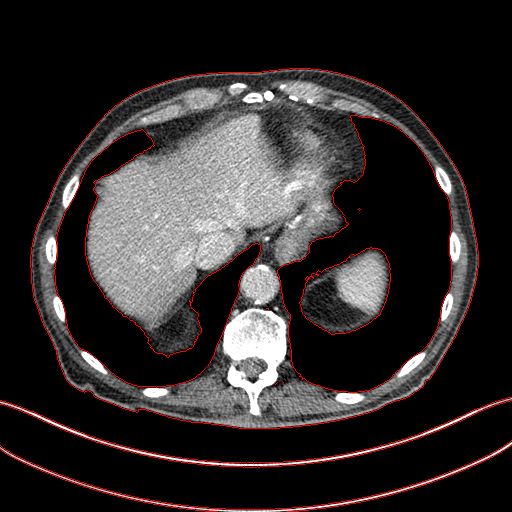

Figure 3: Comparison of denoising performance of different network. The boundary line of different organ extracted from the NDCT image is superimposed on other images. As seen, many pixels are missing around the boundary line in the output of M1

Figure 4: Zoomed version of the ROI taken from the images of Figure 3. In the zoomed version missing boundary pixel is clearly visible in the output of M1.

This section systemically investigates the efficacy of every module proposed in this study. We considered three different networks; first, baseline model(M1), where the inverting block is replaced with dense block, and trained using minimizing mean square distance between two noisy observations(i.e. fsubscript𝑓\mathcal{L}_{f}). Next, two independent baseline model(one for forward mapping, one for reverse mapping) is jointly trained using a linear combination fsubscript𝑓\mathcal{L}_{f}, and rsubscript𝑟\mathcal{L}_{r}, similar to cycle consistent network paradigm. The forward mapping network is used for testing. We refer this model as M2. In both M1, and M2, we increased the depth of the network to make the representation power of these networks comparable with inverting network. Finally, the proposed method, referred as M3. Table 2 depicts the objective evaluation of the three networks using the D1 dataset. Both M2 and M3 use reverse mapping to regularize the network; the influence of the same in the denoising performance is evident from Table 2. Adding cycle consistency loss has improved the performance of the same baseline model significantly. The inverting network performed considerably better than the network M2. It improves PSNR by 0.23dB. As discussed in the above section, in case cycle consistency loss, an additional network is trained, but that does not always guarantee invertibility, whereas inverting network architecture inherently possesses reversibility, which acts as a strong regularizer. In Figure 3 we have shown denoising performance of different networks visually. To demonstrate the requirement of regularization, we first extract the boundary line of the various organ from the NDCT image and superimpose the boundary line on the output of different networks. As shown in Figure 3, many pixels around the boundary line of M1 network output are missing. Using the reverse mapping, the issue of the end-organ missing pixel is successfully overcome in M2 and M3. The granular pattern is also less present in the M3 than M2. The zoomed version of a ROI taken from the images of Figure 3 is given in Figure 4 for better perception. In Figure 5 we give an example of the performance of the invertible network in reverse mapping. Here, the predicted LDCT image is produced by using the predicted clean image of the forward mapping as the input for reverse mapping. As shown, the predicted noisy pattern is similar to the original noise pattern. The same streaking artifacts are present in both the noise pattern; also, the noise variance is different in the various spatial region depending on the signal intensity of the original CT image. It validates that the loss of information in reverse mapping is minimal. Due to the invertible network’s structural advantage, the network also preserves every information present in the input image in the forward mapping.